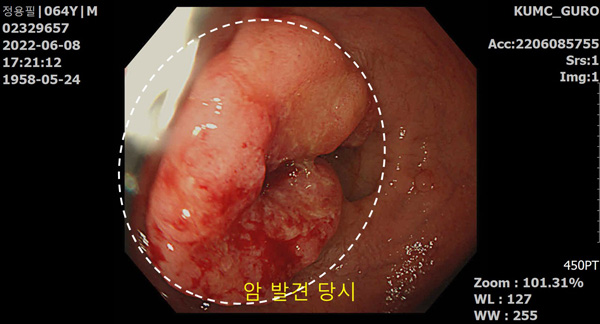

In June 2022, I noticed blood in my stool and went to the hospital for an endoscopy. The result showed my rectal cancer. I was so shocked by the unexpected diagnosis because I had been healthy enough to drink iced coffee even in the winter. Rectal cancer happens when a bulging tumor develops in the tube between the rectum and the anus, and it blocks smooth bowel movements.

Two months later, I went to the hospital again and the doctor said that I needed an urgent surgery, but the cancerous tissue was so large that they had to first reduce its size with chemotherapy and then to do the surgery.

In December, the cancerous tissue became smaller, in which I could get a surgery. But the doctor told me that I should have open-abdominal surgery measuring 30 centimeters wide and 20 centimeters long and remove the rectum. And I would have to undergo restoration surgery in 4 months and have the additional chemotherapy.

Cancerous tissues found